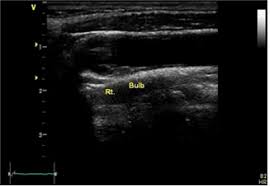

경동맥 동맥류는 경동맥이 국소적으로 확장되어 주머니형으로 돌출되는 질환입니다. 이 상태가 지속되면 파열 위험이 커지므로 조기 발견이 필수적입니다. 경동맥 초음파 검사를 통해 이러한 동맥류를 조기에 발견할 수 있으며, 검사 결과에 따라 적절한 치료 방법을 결정할 수 있습니다. 경동맥 초음파 검사로 알 수 있는 병 중 동맥류는 생명과도 직결될 수 있는 만큼 신속한 대처가 필요합니다.